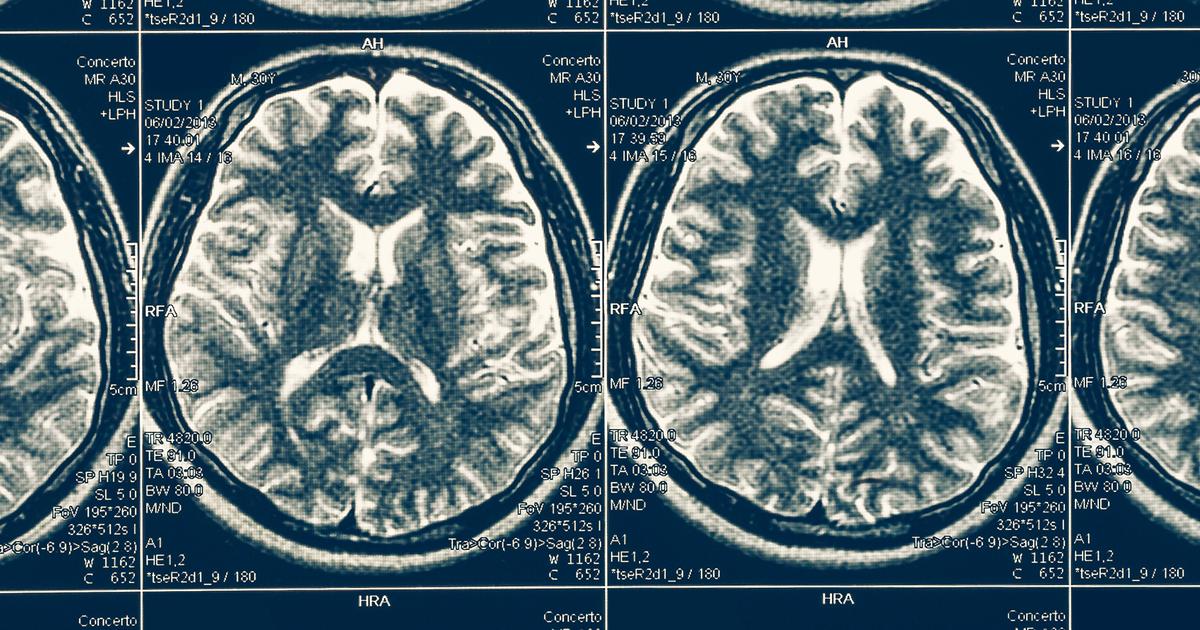

When an individual has a structural abnormality that adversely causes an irregularity in the relationship between the brain tissues and skull, it is referred to as Chiari malformation. As a result of this structural abnormality, the brain tissues are pressed into the spinal canal inappropriately. Most cases of Chiari malformation are present at birth, while others occur during adulthood. Individuals affected by Chiari malformation may exhibit symptoms such as headache at the back of the head, dizziness, extremity numbness, extremity tingling, upper body weakness, upper body sensation loss, difficulty walking, neck pain, trouble swallowing, hearing loss, and balance trouble. Diagnosis of Chiari malformation is made by physical examination, x-rays, CT scans, and MRI scans. Treatment for Chiari malformation may include medication and surgery.